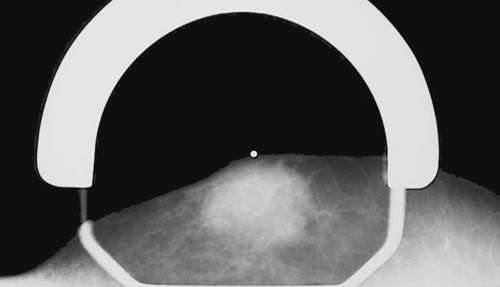

| Male breast cancers are much less common than female breast cancers, perhaps by a ratio of 1000 to 1. Most occur in elderly males and have spread to contiguous structures by the time they are detected, giving them a high stage at diagnosis. The same diagnostic techniques, such as mammography as seen here showing a dense mass, can be utilized for screening and diagnosis. |